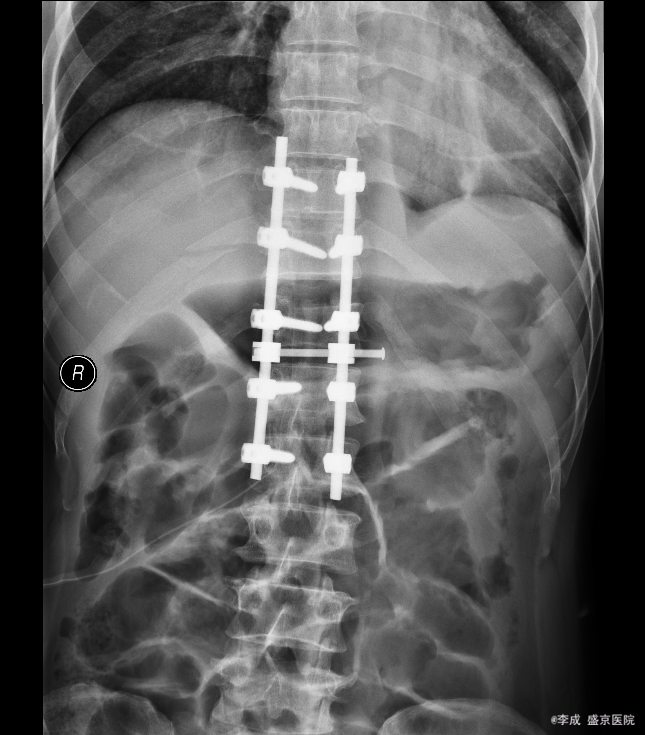

患者入院后完善相关检查,明确诊断,手术指征明确,于2015-11-17日于全麻下行胸椎后路椎板减压椎弓根钉棒系统内固定术,术后经抗炎、止疼等对症治疗后,患者恢复顺利,切口愈合良好,明日可出院。